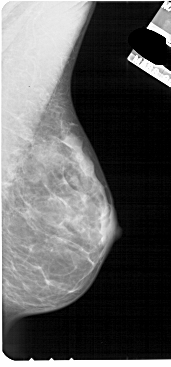

ics_version 1.0 filename A-1841-1 DATE_OF_STUDY 9 8 1996 PATIENT_AGE 45 FILM FILM_TYPE REGULAR DENSITY 4 DATE_DIGITIZED 18 5 1999 DIGITIZER HOWTEK 43.5 SEQUENCE LEFT_CC LINES 4636 PIXELS_PER_LINE 2326 BITS_PER_PIXEL 12 RESOLUTION 43.5 OVERLAY LEFT_MLO LINES 5041 PIXELS_PER_LINE 2626 BITS_PER_PIXEL 12 RESOLUTION 43.5 OVERLAY RIGHT_CC LINES 4936 PIXELS_PER_LINE 2461 BITS_PER_PIXEL 12 RESOLUTION 43.5 NON_OVERLAY RIGHT_MLO LINES 5491 PIXELS_PER_LINE 2551 BITS_PER_PIXEL 12 RESOLUTION 43.5 NON_OVERLAY |